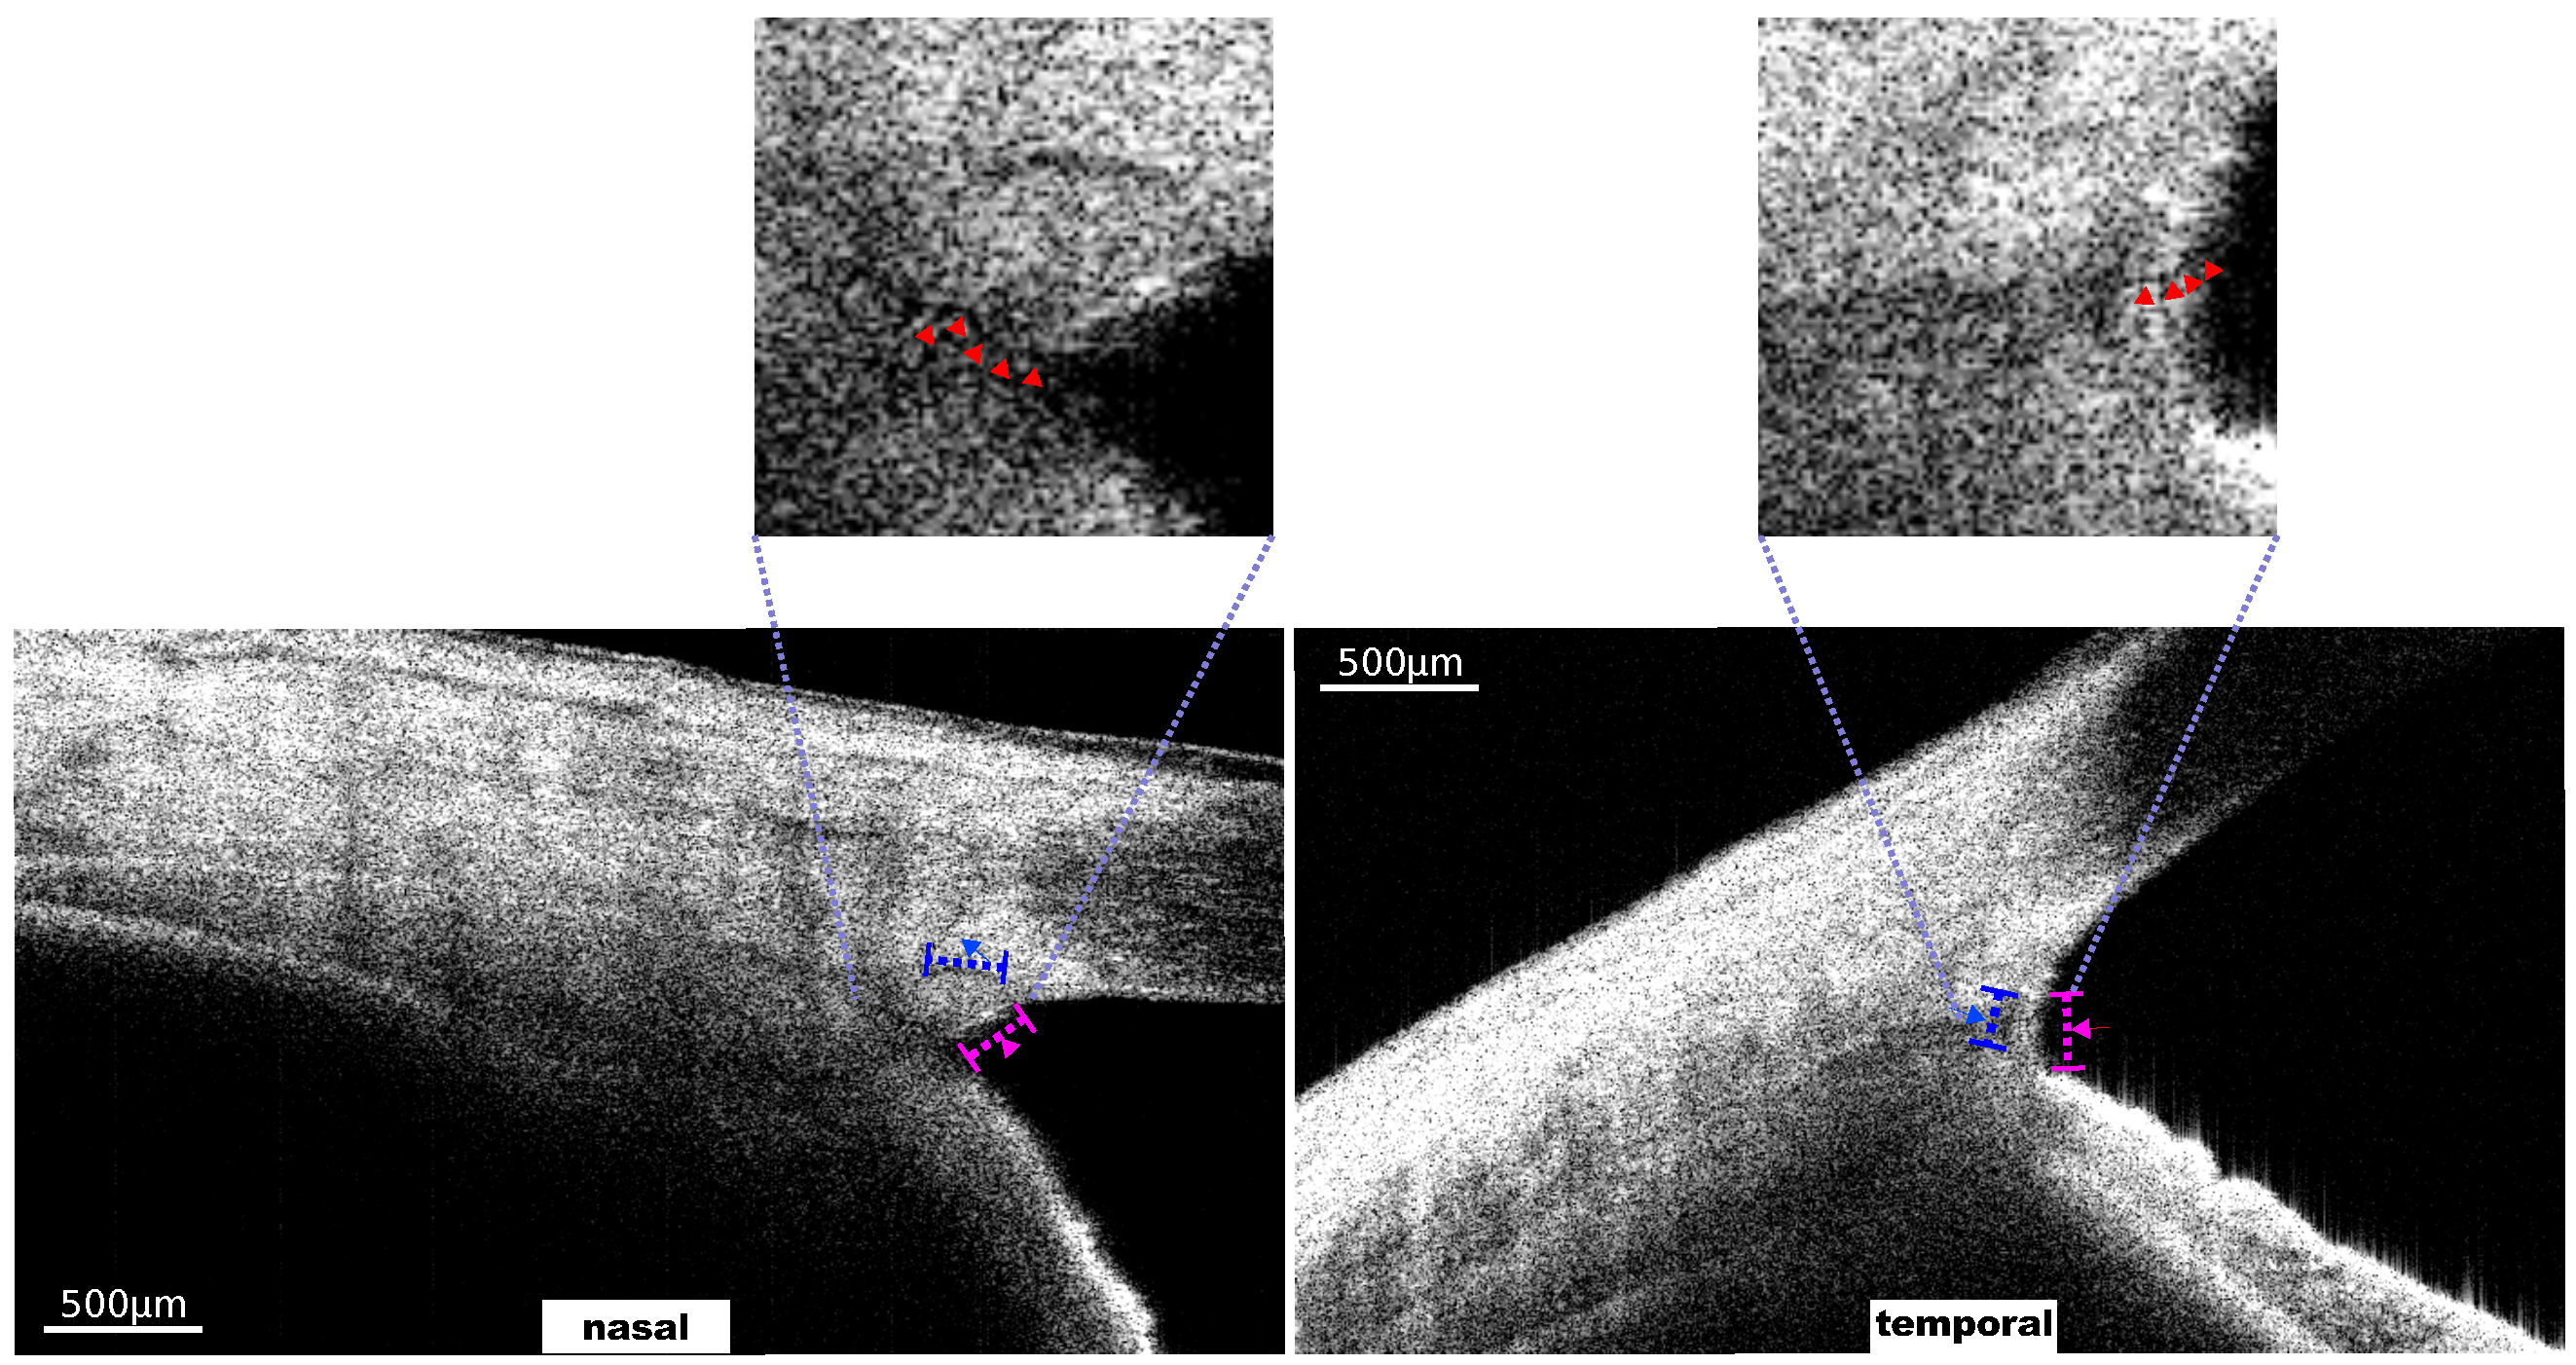

The distribution of the signals in the first two rows of Figure 5 was significantly centered on the outer wall of the SC. Consistencies in the frequency, as well as the amplitude, were confirmed at the same time. The contrast image for these two cases is shown in Figure 6. The SC was identified. In the enlarged view of the TM-SC region, the CCs were identified.

Figure 6. Contrast OCT structural images for subfigures (i) and (ii) of Figure 5. The trabecular meshwork (TM) and Schlemm’s canal (SC) are marked by the pink and blue dashed lines, respectively. In the enlarged view of the TM-SC region, a microtubule structure is marked by the red arrows.